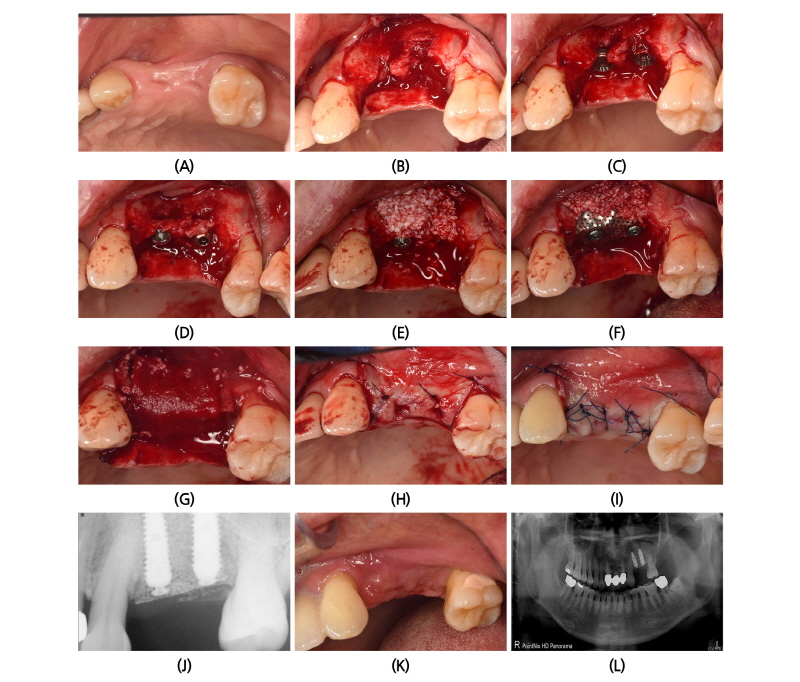

발치 후 약 9주 정도의 치유기간을 기다려 임플란트 식립을 위해 국소마취하에 판막형성을 하였다. 발치와의 치유가 완전하지 않았고, 임플란트 식립 후에는 수직적으로 2-3개의 나사선이 노출 되었다. 구개측 치조골쪽으로 밀듯이 드릴링을 하고 임플란트의 플랫폼(Platform) 부위를 치조골정에서 1.5 mm가량 깊게 식립하였다. 제조자의 추천은 치조골정에서 약 0.5 mm 깊게 식립하는 것을 추천하나 수평적 수직적 골유도재생을 위해서 제조자의 추천보다 약간 더 깊이 식립하는 것이 유리하기 때문이다. 노출된 나사선에는 드릴링 시 얻어진 자가골을 덮고 바깥쪽에는 임플란트 직경의 협설측으로 2 mm 이상의 폭을 만들 수 있도록 충분한 양의 이종골을 덮었다. 상악골의 치밀도가 하악골에 비해 떨어지기 때문에 별도의 피질골제거(decortication)는 실시하지 않았다(Fig. 2A-2E).

본 증례에서는 ㈜네오바이오텍에서 제조한 GBR system을 사용하였고 높이 1.5 mm의 스페이서(Spacer)를 임플란트에 연결한 후에 80도 정도로 접은 무치악용 titanium mesh (E2)를 적용하였다. 상부의 고정은 GBR 전용 덮개나사(Cover screw)를 사용하였다. Colla-tape은 titanium mesh를 덮을 만큼 외과용 가위를 사용하여 절단하고 다듬었다. 그 후 Colla-tape은 마른(dry) 채로 환부에 덮고 창상부위에서 스며 나온 혈액에 의해 자연스레 젖을 수 있도록 적용한 후에 잠시 기다렸다가 협측의 판막에 감장절개를 하여 판막의 긴장도를 낮춰준 후에 수평누상봉합을 2군데 실시하여 협설측의 판막이 인접한 근처에 올 수 있도록 한 후에 단속봉합으로 마무리하였다. 이러한 이중-봉합법은 판막의 긴장도를 줄이며 일차유합의 확률을 높일 수 있는 방법으로 추천된다(Fig. 2F-2I). 수술 후 촬영한 구내 방사선 사진에서 #24 부위 임플란트의 GBR 전용 덮개나사가 제대로 고정이 되지 않은 것을 알 수 있다. 그러나 높이 올라온 것도 아니고, 일차 유합에 방해되지 않아 그냥 두기로 했다(Fig. 2J). 봉합사는 4-0 나일론사를 사용하였으며 2주 후에 봉합사 제거 시 완벽한 일차유합을 이루고 있었고 염증이나 2차적인 감염의 징후가 없었다(Fig. 2K, 2L).

4개월 후까지 titanium mesh가 노출되지 않았음을 확인할 수 있었고 uncovering을 위해 국소마취하에 titanium mesh를 제거하였다. 협설측으로 골양조직이 충분한 양이 생긴 것을 관찰할 수 있었으며 치유지대주를 연결한 후에 유경피판을 형성하여 협설측 판막을 회전하여 봉합하였다(Palacci technique). 상악 구치부에서 이 방식은 치유지대주 주변의 건강한 잇몸 형성에 도움이 된다(Fig. 3).